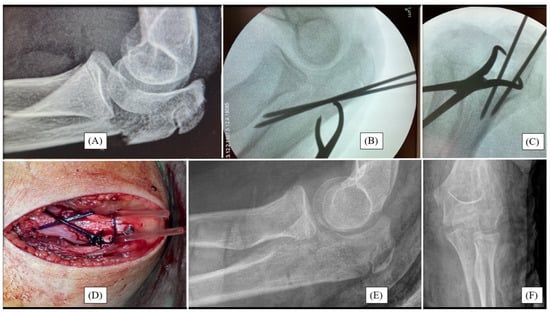

3.2. Case 2